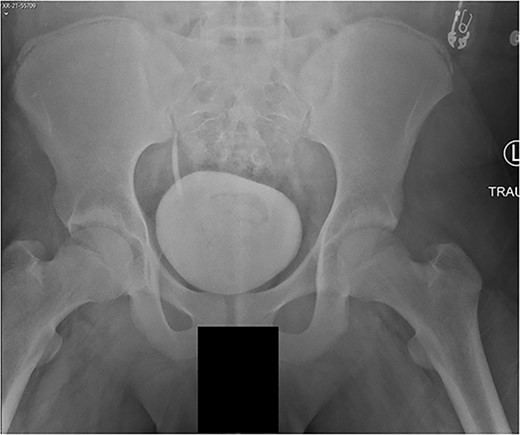

A 14-year-old boy sustained closed right and left mid-shaft femur fractures (Right OTA 32-A3, Left OTA 32-B2) after an all-terrain vehicle accident (Fig. 1a and b). The patient was classified as obese with a BMI of 37. Bone age was determined to be approaching skeletal maturity and so a rigid trochanteric entry femoral rod was selected for the implant [15, 16] (Fig. 2). Laboratory derangement included hyperphosphatemia and hypoalbuminemia. Therefore, additional measures to include early fracture stabilization and the RIA adjunct was selected for our patient [17].